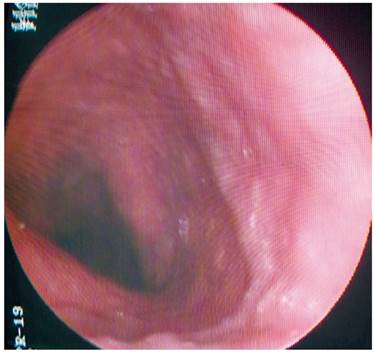

La paciente presenta un antecedente relevante de válvula ventrículo-atrial de Hakim desde los 20 años, por causa de un pseudotumor cerebral. Entre tanto, en 2010 se encontró una várice esofágica superior, mediante una esofagogastroduodenoscopia (EGD) (Figura 1). A partir de este examen le fue descartada una patología venosa obstructiva, luego del resultado anterior, con persistencia de la várice esofágica superior y sin estigmas de sangrado o de riesgo en 2016.